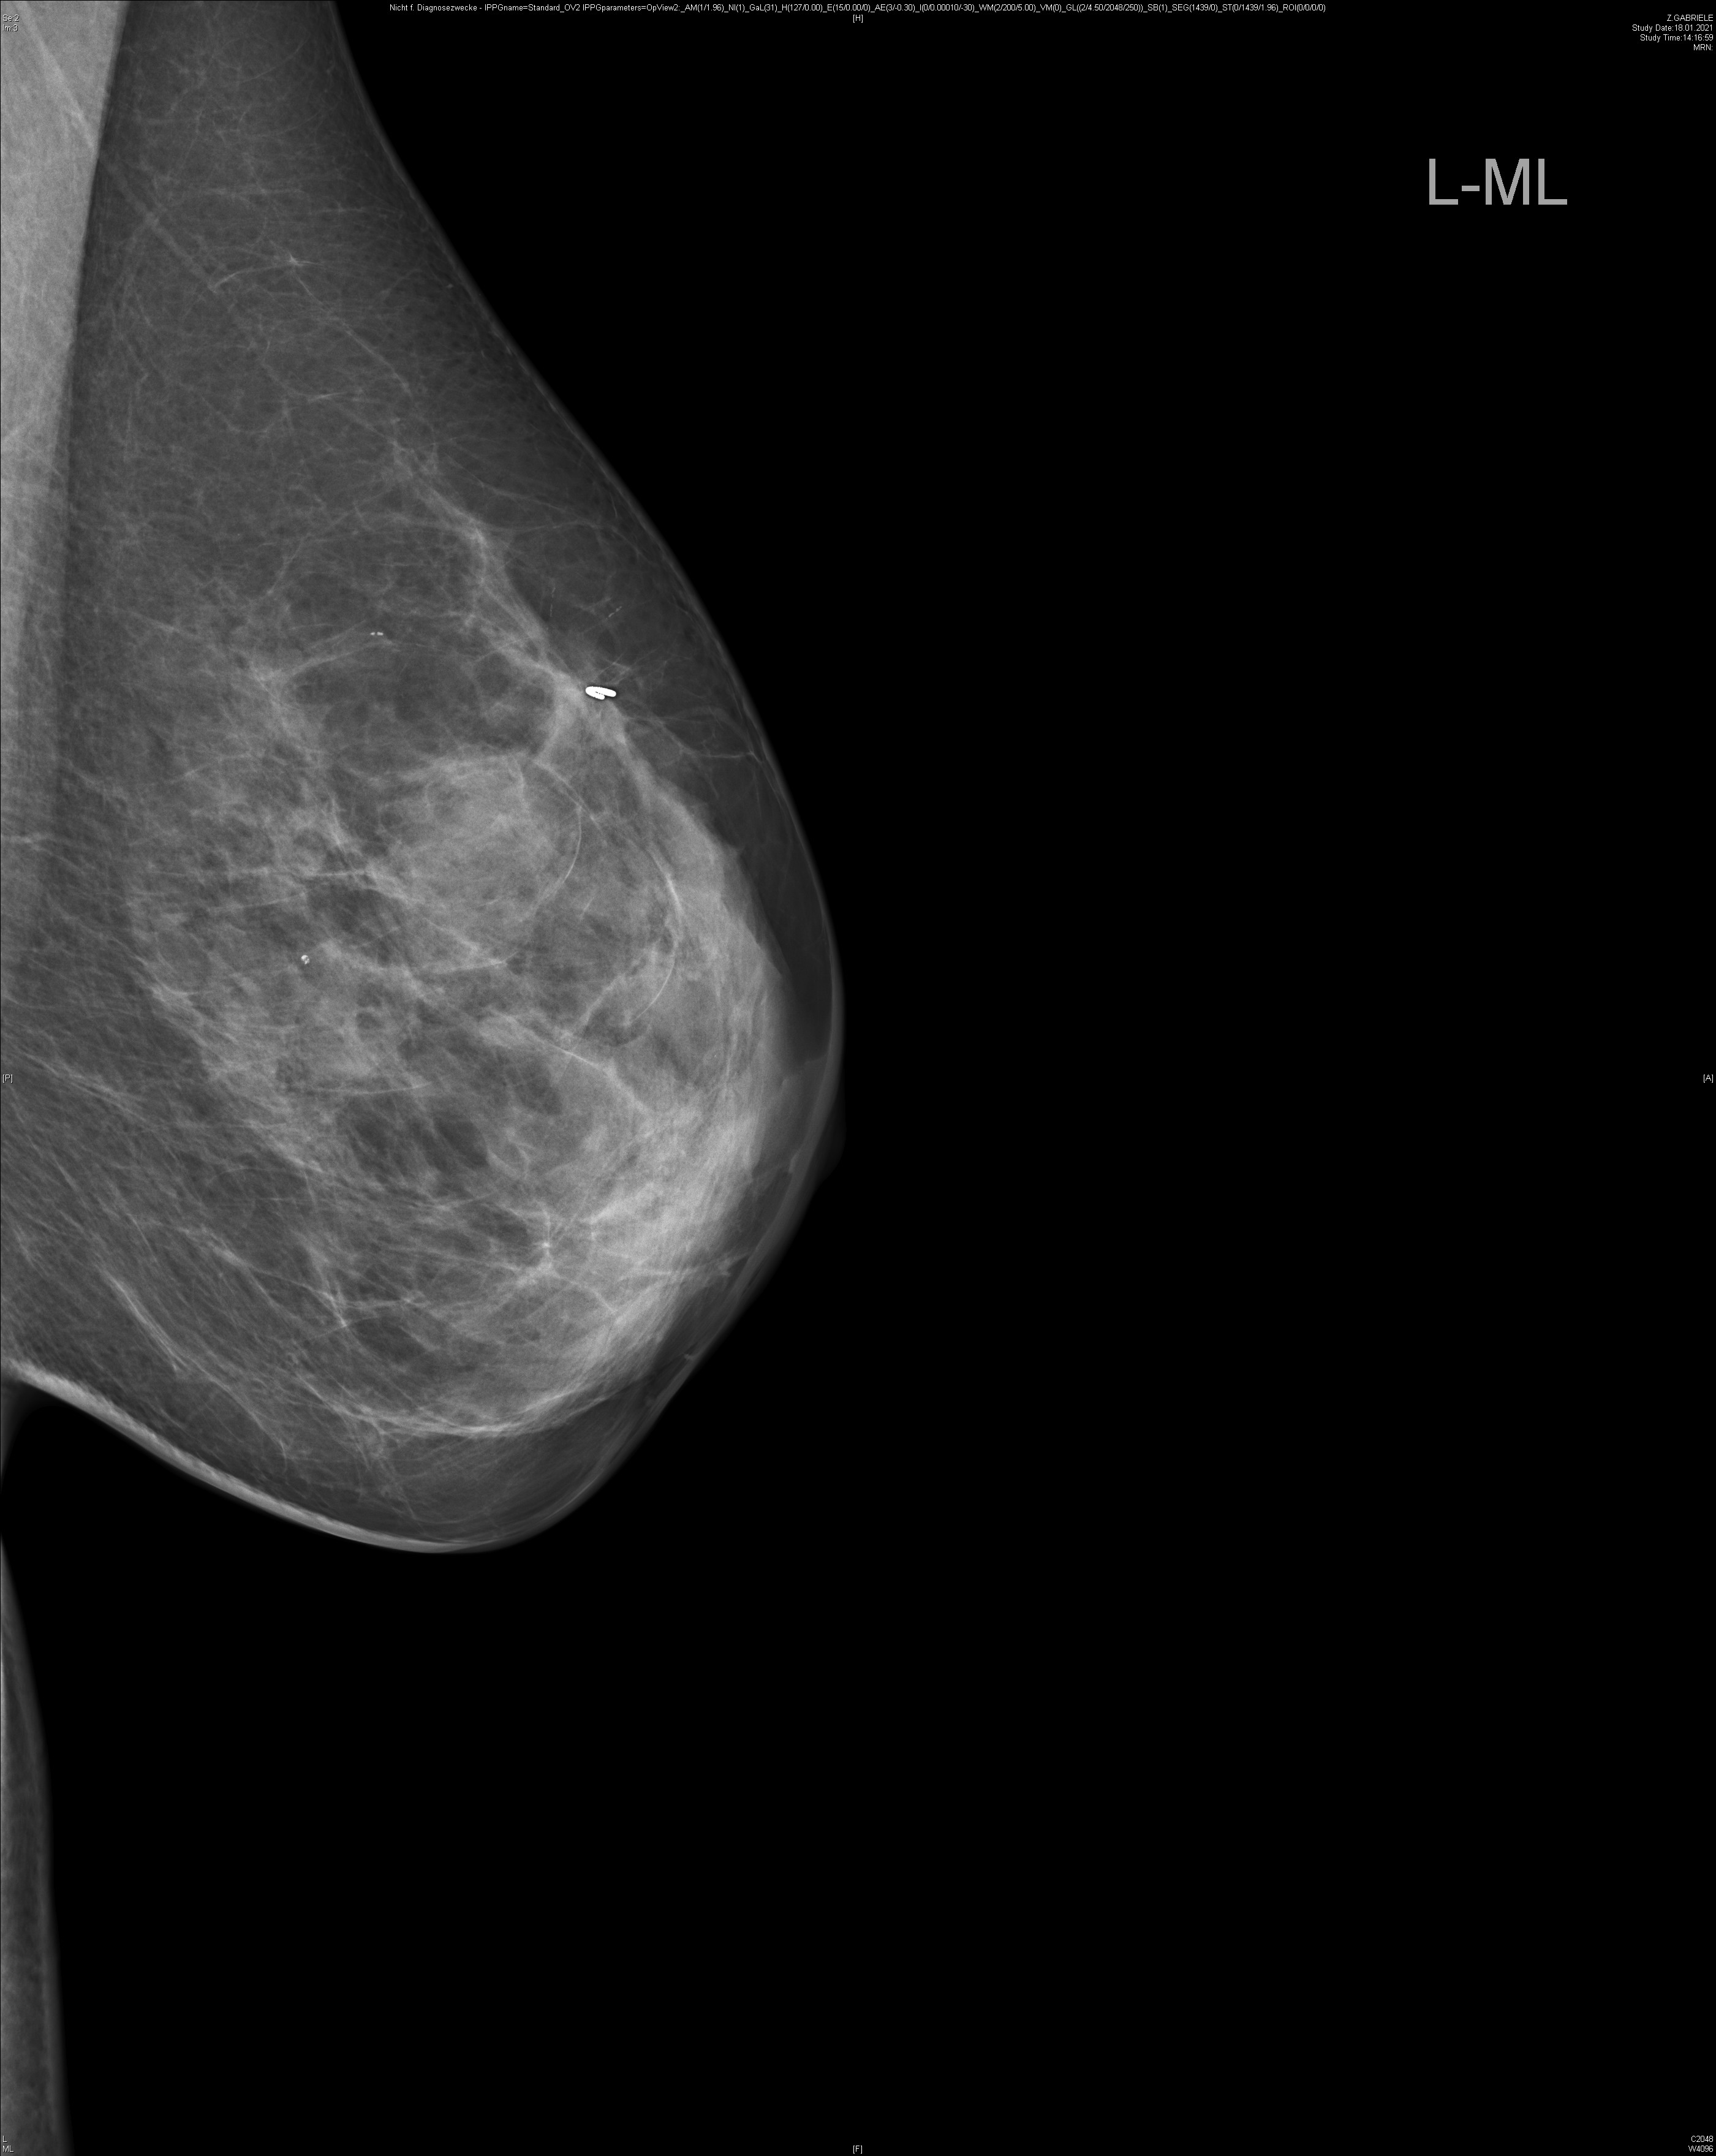

Bei rund einem Drittel der Brustkrebspatientinnen, die eine sogenannte neoadjuvante, der Operation vorgeschaltete Chemotherapie erhalten, bildet sich der Tumor vollständig zurück. Operiert werden sie bislang trotzdem, denn erst die Gewebeentnahme und -analyse bei der Operation zeigt eindeutig, ob alle Krebszellen abgestorben sind. Einen Ausweg aus dieser Problematik könnte ein lernender Algorithmus bieten, der gleichzeitig mehrere Faktoren berücksichtigt. Er ermöglicht laut ersten Studienergebnissen eine zuverlässige Diagnostik, wie Wissenschaftler des Brustzentrums der Universitäts-Frauenklinik Heidelberg unter anderem mit Kollegen vom MD Anderson Cancer Center, Houston, USA, und Royal Marsen Hospital, London, Vereintes Königreich, aktuell in einem Highlight-Artikel im European Journal of Cancer berichten. Sie testeten im Rahmen der RESPONDER-Studie verschiedene Methoden des maschinellen Lernens anhand der Daten dreier in den letzten Jahren publizierter Studien aus Heidelberg, den USA und Südkorea mit insgesamt 457 Brustkrebspatientinnen. „Mit Hilfe dieses intelligenten Diagnostikwerkzeugs könnte zukünftig rund einem Drittel der Frauen mit vorgelagerter Chemotherapie und gutem Ansprechen die anschließende Operation erspart werden,“ so Studienleiter Prof. Dr. Jörg Heil, Leiter des Brustzentrums an Universitätsklinikum und Nationalem Centrum für Tumorerkrankungen Heidelberg. Bevor es soweit ist, muss der Algorithmus allerdings seine Zuverlässigkeit noch in einer weiteren Studie unter Beweis stellen.

Die Frage, wie gut die Chemotherapie im Vorfeld der Operation angeschlagen hat, lässt sich – das haben aktuelle Studien gezeigt, die von den Heidelberger Wissenschaftlern federführend durchgeführt wurden – weder mit bildgebenden Untersuchungen noch mittels Biopsie zweifelsfrei beantworten. „Das Problem bei der alleinigen Biopsie ist, dass das Tumorgewebe bei Brustkrebs häufig heterogen ist und entsprechend uneinheitlich auf die Therapie anspricht“, erläutert Seniorautor Heil. „Nur weil die Gewebeprobe aus der Biopsie keine Krebszellen mehr enthält, heißt das nicht, dass der gesamte Tumor abgestorben ist.“ Eindeutige Klarheit bringt bislang erst die Untersuchung des bei der Operation entnommenen Gewebes. Die Behandlungsrichtlinie sieht daher vor, dass alle Frauen dem ursprünglichen Tumor entsprechend operiert werden. So wird Gewebe entnommen, obwohl möglicherweise gar kein Tumor mehr vorhanden ist.

Um den Frauen mit sehr gutem Ansprechen auf die Chemotherapie eine unnötige Operation zu ersparen, machten sich die Heidelberger Wissenschaftler Methoden des Maschinellen Lernens zunutze. Dabei wird ein rechnergestütztes System darauf trainiert, aus der gemeinsamen Analyse verschiedener Faktoren Zusammenhänge zu erkennen und darauf basierend eine belastbare Diagnose zu stellen. In den Algorithmus, der sich am zuverlässigsten erwies, fließen insgesamt 27 Faktoren ein, darunter unter anderem Alter der Patientinnen, Merkmale des Tumors und die Ergebnisse einer bestimmten Art der Biopsie (Vakuum-assistiert). In einer internen wie externen Überprüfung mit Patientendaten aus den verwendeten Studien übersah das System keinen verbliebenen Tumor, was für eine hohe diagnostische Sicherheit des Algorithmus spricht.